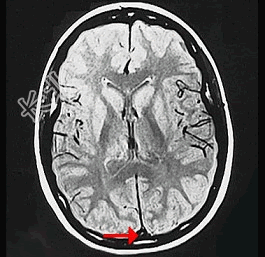

- 单项选择题如图箭头所示,应属于大脑的哪个部位 ( )

A、窦汇

B、横窦

C、直窦

D、上矢状窦

E、下失状窦